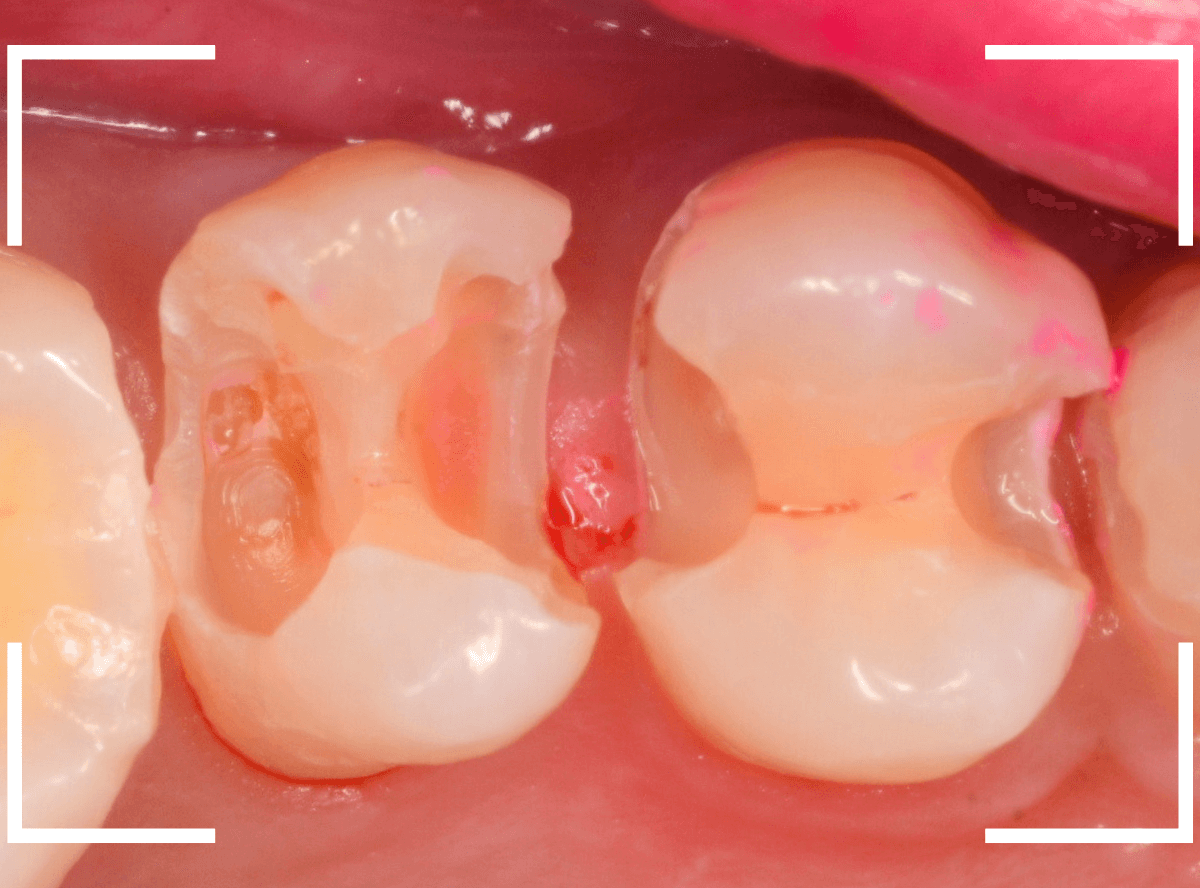

今回は、「上の奥歯が噛むと痛い」という訴えで来院された患者さんのケースです。

初見では、どこが悪いのかはっきりわかりません。

レントゲン写真で確認すると、 奥歯はどの歯も深い虫歯ですが、特に、奥から2番目の歯が深い虫歯で、痛みの原因だと思われます。

痛みが出るまで様子見た虫歯はどうなっているのでしょうか。